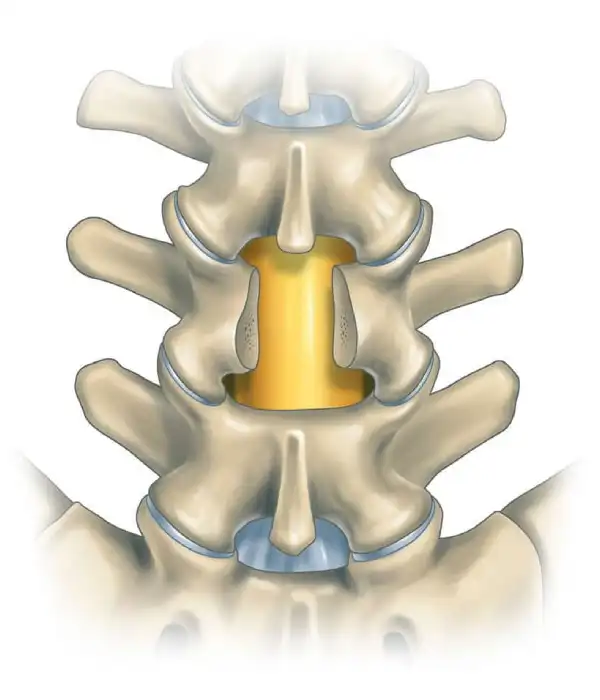

Comprehensive View of Cervical Discectomy

Anterior Cervical Discectomy Fusion

Anterior Cervical Discectomy